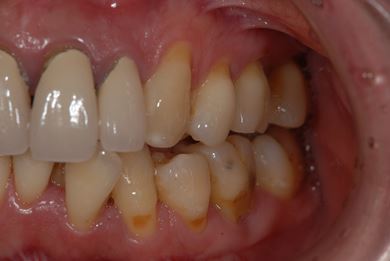

| 性別/年齢 | 女性 / 40歳 | ||||||||||||||||||||||||||||||||

| 主訴 | 前歯のつけ根の黒い部分を見えないようにしたい。 | ||||||||||||||||||||||||||||||||

| 治療方針 | 上顎前歯をセラミック治療にて審美的回復を行う。 | ||||||||||||||||||||||||||||||||

| 治療内容 | オールセラミッククラウン4本(セラミック用土台4本) | ||||||||||||||||||||||||||||||||